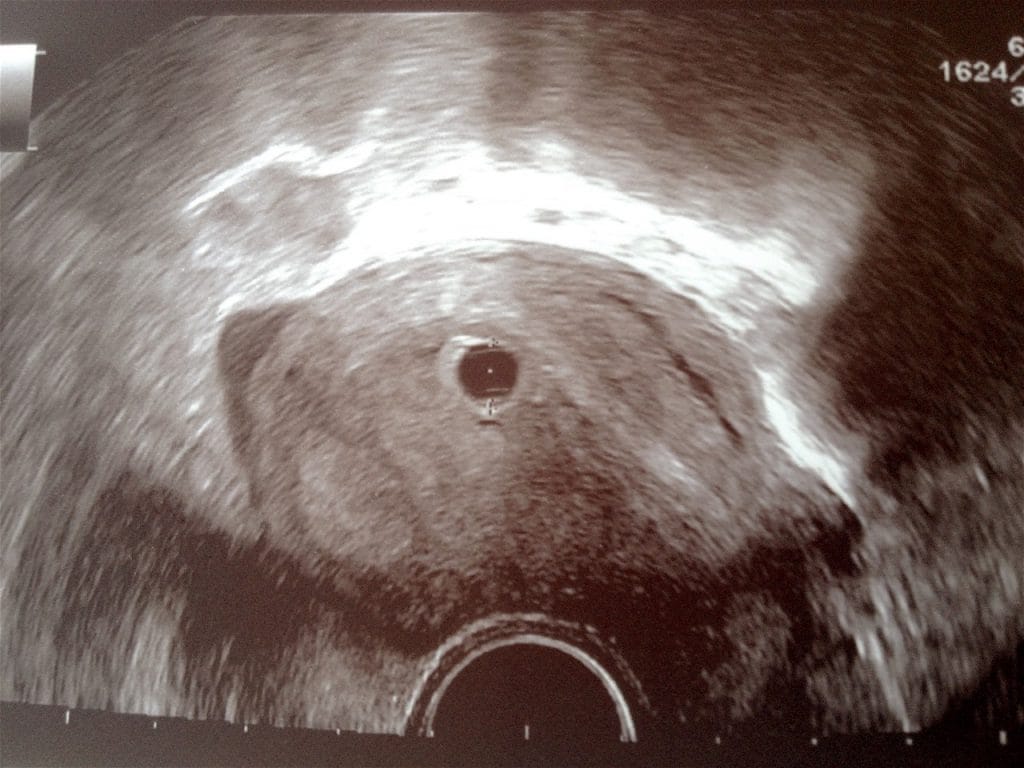

Na ultrazvoku smo sicer vrečko že videli, plodka pa žal še ne. Za trenutek sem se kar pošteno prestrašila, ampak me je ginekologinja pomirila. Izpolnila materinsko knjižico. Povedala, da ni nič hudega, da sem očitno zanosila malce kasneje in da se čez 14 dni zopet vidiva in preveriva napredek. Po ultrazvoku in izpolnjevanju materinske knjižice sem imela še pogovor, v katerem me je sestra opomnila na nekaj precej pomembnih stvari v nosečnosti. Seveda se večine spomnim, priznam pa, da mi je ušlo iz spomina, kako pomembne so tudi ribice na mojem jedilniku. Mož sicer ne bo ravno navdušen, ampak glede na izkušnje do sedaj, ne bo prevelik problem.